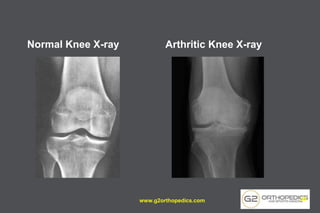

Normal Knee X-ray Arthritic Knee X-ray

• 31.